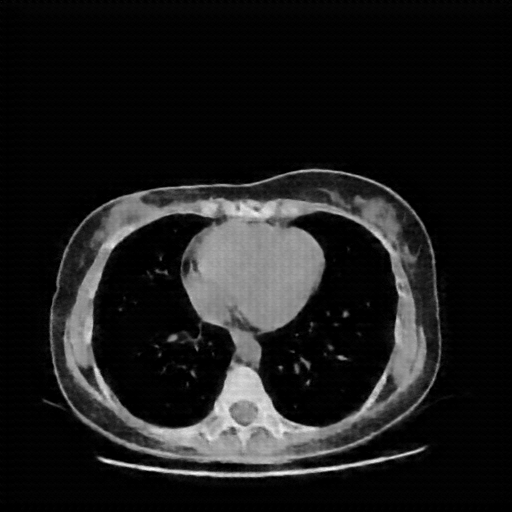

Image Grid

4Γ—3 grid: Rows show different image types (Original NATIVE, Reconstructed NATIVE, Original VENOUS, Generated VENOUS), Columns show windowing techniques (No Window, Lung Window, Mediastinum Window)

Original VENOUS CT scan

Lung window (WL -600, WW 1500 β†’ Low βˆ’1350, High +150)